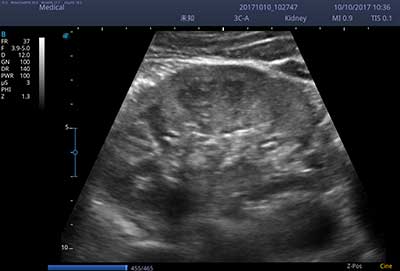

E3便携式彩色多普勒超声诊断系统拥有专业超声技术平台、高度集成化的硬件模块和结构设计、简便的操作流程、支持三探头接口全激活,兼顾了优质图像、轻便机身以及台便两用的临床使用需求。无论在常规超声科门诊检查,还是在急诊、麻醉、ICU、户外等各种应用场景。都能给您带来流程的操作体验。